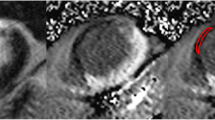

This rise in contrast with use of 80 kV is reflected by the evaluation of image quality according to the criteria explained above (Fig. 4). Inter-rater agreement in the evaluation of image quality was good (weighted kappa=0.72). High contrast between LE, viable myocardium and left ventricular cavity explains best image quality at 5 or 10 min and use of 80 kV and 800 mAs (Figs. 5, 6 and 7).

MR and MSCT images of a transmural antero-lateral infarction. a On the MR image, arrows indicate the zone of late enhancement. The low signal area at the centre of infarcted tissue (cross) corresponds to areas of “no-reflow”, caused by microvascular obstruction in the setting of reperfusion. MSCT images are shown b at 3 min with 80 kV/800 mAs, c at 5 min with 80 kV/400 mAs, d 80 kV/800 mAs, e 120 kV/400 mAs and f 120 kV/800 mAs. Scans g and h were obtained at 10 and 15 min with 80 kV/800 mAs each. Images show good correlation with MRI contrast phenomena, whilst LE volume increases over time. Comparing 80 with 120 kV, the latter reduces image noise with no gain in image quality due to better contrast at 80 kV. Reduction of current, on the other hand, degrades image quality through increase of image noise. At 5 min, HU for blood, viable myocardium and LE were 165, 97 and 135 at 80 kV or 108, 70 and 96 at 120 kV

aMRI showing a transmural antero-lateral infarction with both zones of late enhancement (arrows) and “no-reflow” (cross). d In this example, best CT image quality is provided at 5 min and use of 80 kV/800 mAs. f Application of 120 kV/800 mAs slightly reduces image noise at the cost of contrast between tissues. c, e At both 80 kV and 120 kV, lowering of tube current to 400 mAs leads to strong increase of image noise and deterioration of image quality. At 5 min HU for blood, viable myocardium and LE were 214, 122 and 182 at 80 kV or 123, 80 and 126 at 120 kV. b At 3 min 80 kV/800 mAs, there is incomplete enhancement of the infarct zone with dominance of the “no-reflow” area. g At 15 min 80 kV/800 mAs, there is still considerable contrast to non-viable myocardium. However, washout with low contrast to viable myocardium and blood results in poor delineation of cardiac structures and degradation of image quality